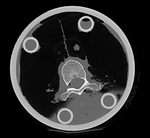

this is the fixed reference image. All images are aligned into this space lleft this is the moving image. The transform is calculated by matching this to the reference image

fixed image/target moving image

We have 2 in vitro CT scans of a human thoracic spine, before and after application of a controlled structural damage. We apply a rigid registration to bring the two images into alignment. Because the container tube and fixtures add image content that is "distracting" to the registration, we crop both images to contain just the vertebra of interest. Also the spines were not imaged in the same orientation, and as consequence we have an inverted z-axis in one of the images we have to correct first. Finally the two images have very different spatial origins (as defined in original DICOM header), so we need to recenter first before running the registration.